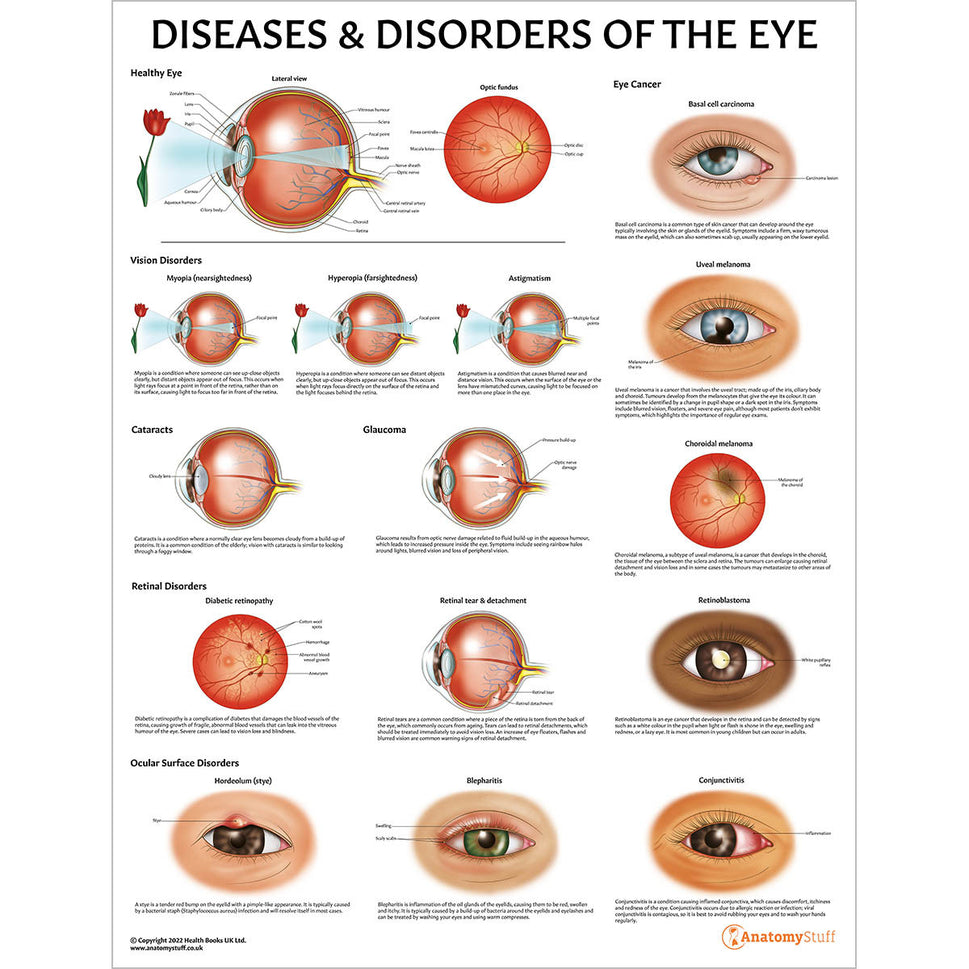

Enhance medical education with our collection of digestive system anatomical models including the stomach, liver, gallbladder, pancreas & colon models. Discover the anatomy of healthy organs as well as common gastrointestinal diseases such as stomach ulcers, gallstones and liver cirrhosis. Our digestive system anatomy posters are ideal for study and patient education.

At AnatomyStuff we stock a diverse range of digestive system anatomical models to suit your training needs. From budget models and affordable medical education posters to highly advanced 3D printed bowel models, you can transform medical training and patient education. As well as our own exclusive collection, we are proud resellers of 3B Scientific, Anatomy Lab, Denoyer-Geppert Science Company, ESP Models, Erler Zimmer and GPI Anatomicals. Explore our exclusive collection of digestive system anatomy charts, posters, fine art prints and digital anatomy study guides. Discover the anatomy of key organs like the liver, stomach, pancreas and bowel as well as the pathophysiology of common conditions like peptic ulcer disease, coeliac disease, IBD and much more. We have anatomy posters suitable for school children all the way up to medical degree level. From a liver anatomy poster to a digital study guide all about common GI disorders, find exactly what you need right here to enhance medical training and patient education.